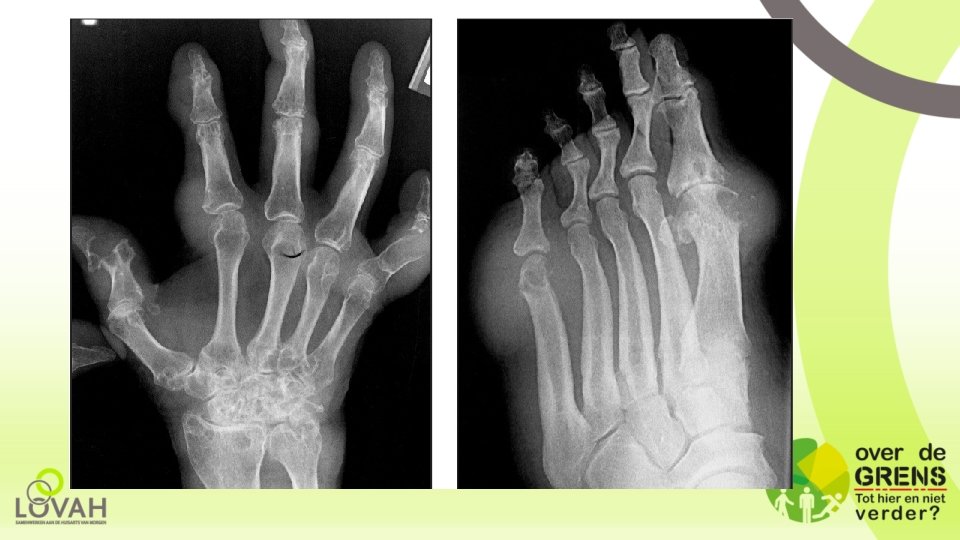

NHG-Standaard Artritis (jicht): wat kan beter? • Percentage podagra 90%. Tip: geldt alleen voor “genetische jicht” • Percentage 20% jichtpatiënten heeft nierinsufficiëntie. Tip: onjuist. Vaak direct topheuze jicht en geen acute artritis in begin. • Tip: Jichtcalculator gebruiken voor 80% zekerheid jicht en beslissen wel/geen punctie nodig. • Tip: Stigmatisering ECHT wegnemen door niet bij causale relatie tussen voedsel/drank te zetten “nog niet bewezen”. • X-foto’s zijn niet nodig. Tip: maak bij frequente aanvallen/verdenking tophi wel X-voeten/handen om erosies op te sporen.